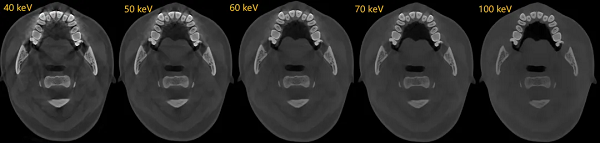

可靠的诊断始于清晰的影像。神农·云CT全新升级双能技术,能从物理层面有效识别并分离由金属植入物产生的伪影,显著降低其对周围关键解剖结构的干扰。

这项技术为种植规划提供了干净、可靠的影像基础,使医生能够清晰地辨识牙槽骨形态、骨小梁结构、神经管走向以及邻牙关系,将诊断依据从基础的“看得见”提升至精准的“看得准”,为后续每一步决策筑牢安全基石。

双能技术被称为传统成像的颠覆性技术,其不仅能实现对组织伪影的有效去除,更能特异性地对组织进行特殊处理,如去钙图/有效原子序数图等。